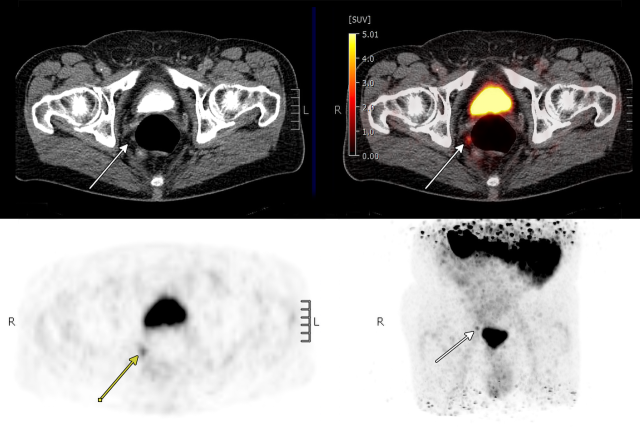

PSMA PT/CT scan

A newer imaging tool, PSMA PET/CT, uses a radioactive tracer that binds to prostate-specific membrane antigen, a protein found on most prostate cancer cells. This allows doctors to detect very small clusters of cancer that would otherwise be invisible on standard scans, making it more sensitive than conventional imaging for detecting prostate cancer recurrence and allowing clinicians to see whether the disease is confined to the prostate bed, has spread to nearby lymph nodes, has traveled to other parts of the body, or is not yet visible. By clearly showing the location and extent of recurrent disease, PSMA PET/CT helps doctors tailor treatment to each patient’s needs. The information can guide personalized decisions, such as whether to expand radiation to the whole pelvis, deliver higher doses to visible tumors, or add hormone therapy.

Researchers tracked long-term outcomes such as cancer recurrence, spread to other parts of the body, and the need for additional treatments. About 60% of patients had cancer detected on PSMA PET/CT scans, including many whose disease had already spread beyond the prostate bed to lymph nodes or bones, allowing clinicians to adjust treatment strategies accordingly.